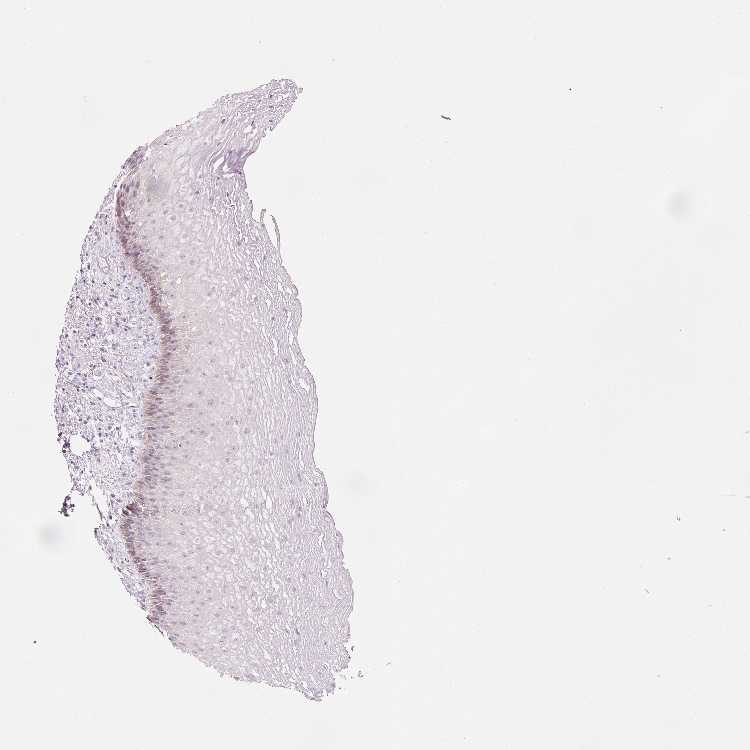

TISSUE PRIMARY DATA ESOPHAGUS Show tissue menu

ESOPHAGUS - Antibody stainingi

Antibody staining in the annotated cell types in the current human tissue is reported as not detected, low, medium, or high, based on conventional immunohistochemistry profiling in selected tissues. This score is based on the combination of the staining intensity and fraction of stained cells.

Each image is clickable and will lead to virtual microscopy that enables deeper exploration of all samples and also displays staining intensity scores, fraction scores and subcellular localization as well as patient and tissue information for each sample.

Antibody HPA041226Antibody HPA048236Antibody HPA053623

Squamous epithelial cells LowMediumLow